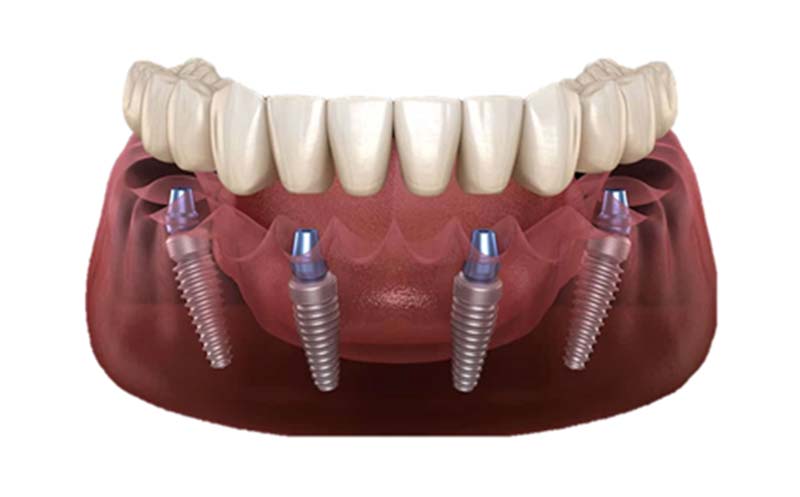

一、All-on-4 全口植牙技術

技術原理

利用四根植體(前2直、後2斜)固定整排假牙,避免補骨,縮短療程。

適合對象

- 下顎或上顎缺牙

- 骨質流失但還不嚴重者

- 想快速重建、節省預算者

優點

- 當天拔牙、當天裝牙(視條件)

- 相對便宜、穩定度高

- 外觀自然、清潔方便

缺點

- 有些狀況仍需補骨

- 需配合醫師評估骨角度